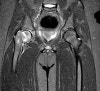

CT, MRI은 골단의 이동을 알기쉬워 조기진단에 유리합니다.

MRI : 대퇴골두 골단 분리증(Slipped capital femoral epiphysis : SCFE)